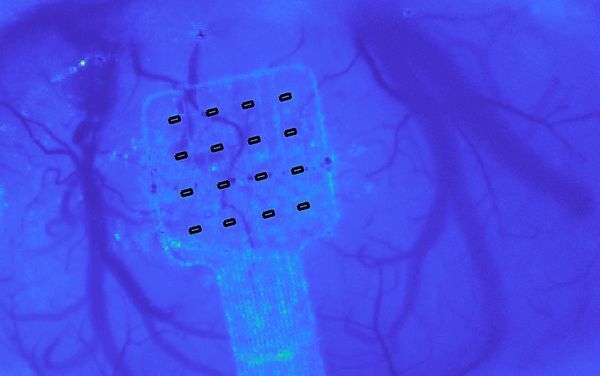

Graphene sensors can hear your brain whisper

"A newly developed graphene-based implant can record electrical activity in the brain at extremely low frequencies and over large areas, unlocking the wealth of information found below 0.1 Hz. This technology, which will be showcased in the Graphene Pavilionat Mobile World Congress in Barcelona (25-28 February 2019) was developed by Graphene Flagship partners at the Barcelona Microelectronics Institute (IMB-CNM, CSIC), the Catalan Institute of Nanoscience and Nanotechnology (ICN2), and ICFO. The prototype was adapted for brain recordings in a collaboration with the Biomedical Research Institute ‘August Pi i Sunyer’ (IDIBAPS). The study, just published in Nature Materials, describes how this ground-breaking technology will enhance our understanding of the brain and pave the way for the next generation of brain-computer interfaces. The body of knowledge about the human brain is keeps growing, but many questions remain unanswered. Researchers have been using electrode arrays to record the brain's electrical activity for decades, mapping activity in different brain regions to understand what it looks like when everything is working, and what is happening when it is not." [...]